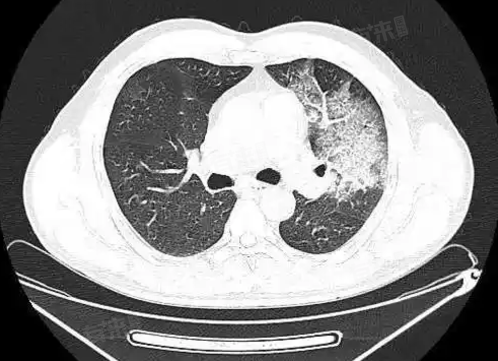

2、影像学表现

- 在胸部X光或CT检查中,左肺纤维灶通常表现为密度增高的条索状或斑片状阴影,边界相对清晰,其形态和分布可能因个体差异和病因不同而有所不同。